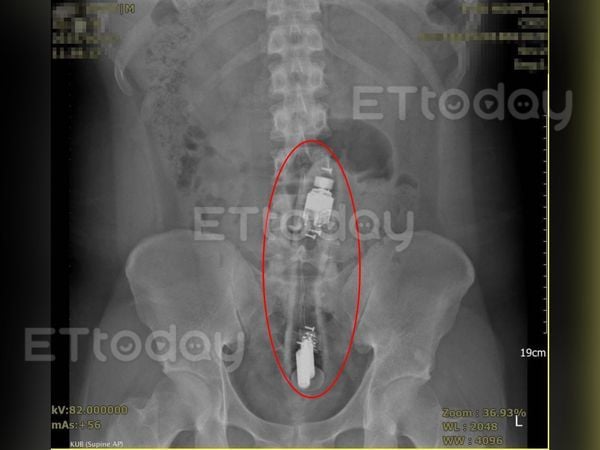

X-ray reveals vibrator lodged deep in the colon

Upon examination, Dr Chen identified a hard mass inside the patient’s anus. An X-ray confirmed the presence of a long, rod-shaped object measuring between 15 and 20cm, which had travelled up to the sigmoid colon.

Source: ETtoday